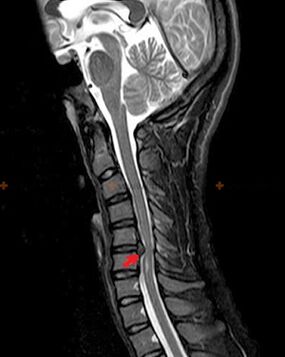

Osteochondrosis is an x-ray diagnosis, since a detailed clinical picture is available only at the moment of exacerbation, while changes in the spine can occur with complete subjective well-being of a person.Without an X-ray examination, we can only talk about suspected osteochondrosis, because similar symptoms can be caused by other diseases (myositis, vertebral neoplasms, and others).

To diagnose osteochondrosis, the following research methods are used: radiography (preferably with functional tests), MSCT and MRI.The latter study is most preferable due to the fact that it allows one to very clearly visualize the condition of the intervertebral structures.

The presence of the changes described above, as well as changes in the structure of the intervertebral disc, detected by MSCT and MRI, serve as reliable signs confirming the presence of osteochondrosis.